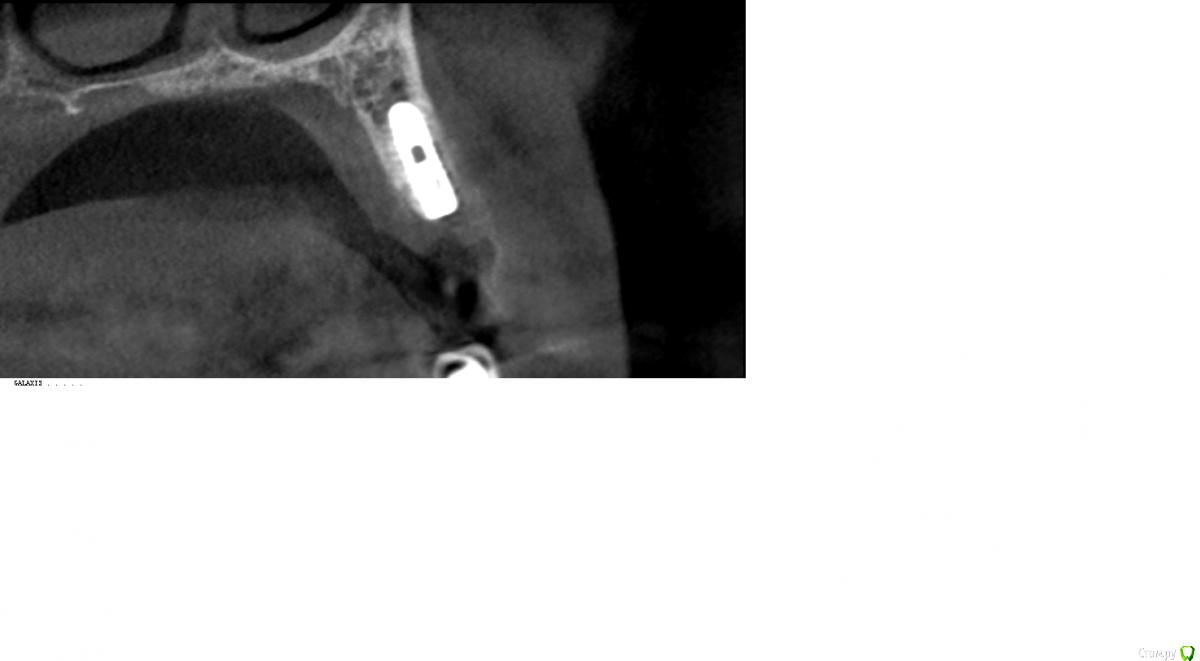

Robinbobin Опубликовано 9 февраля, 2016 Поделиться Опубликовано 9 февраля, 2016 Представляю вашему суду работу с хирургическим шаблоном были установлены имплантаты ИРИС в области 2.5 зуба 3D заполнение и немедленная нагрузка.коронки были изготовлены прямым методом 13 Ссылка на комментарий

Robinbobin Опубликовано 10 февраля, 2016 Автор Поделиться Опубликовано 10 февраля, 2016 контроль с пинами есть,а с имплантатами? 1 Ссылка на комментарий